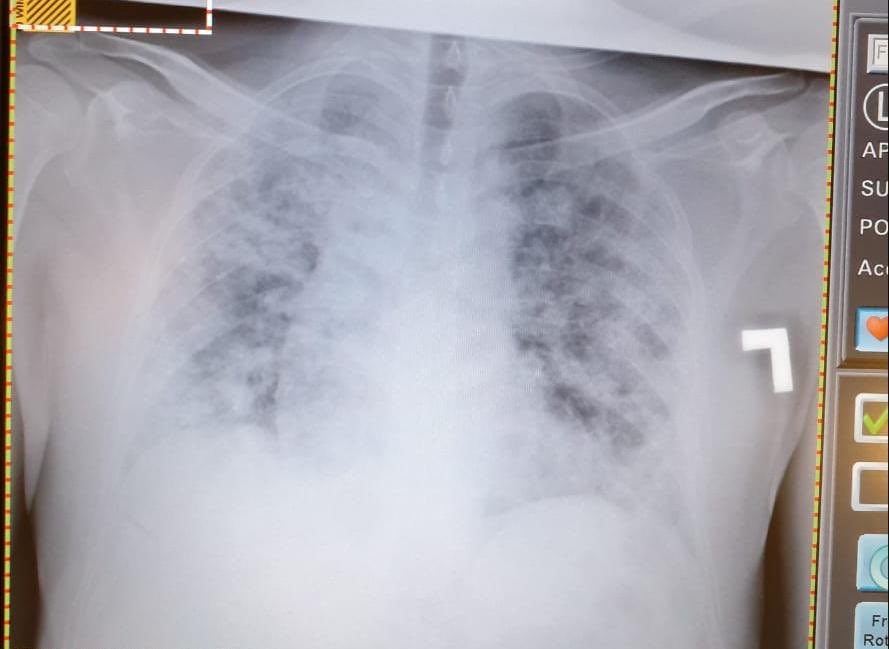

٤-هذه صورة للرئة الطبيعية قبل الالتهاب وصورة بعد دخول الرئة في متلازمة الضائقة التنفسية الحادة ARDS (هذا البياض الشديد عبارة عن التهاب حاد) ويصعب تبادل الغازات التنفسية وتصبح متصلبة ولاتستطيع العمل ومن ثم يتم وضع المريض علىً جهاز تنفسي ..